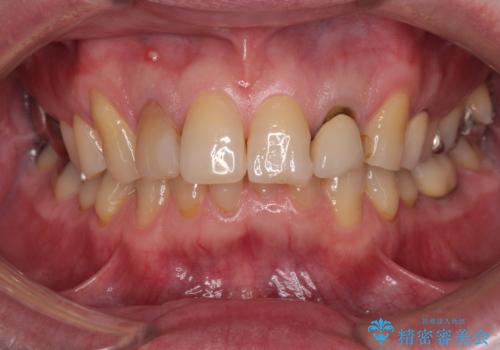

- 前歯の色味が気になるとのことで来院された患者様です。左上の2番目の歯の歯茎のラインと被せものの境目の適合が悪い状態だったのでオールセラミッククラウンによる補綴治療を行っていくことになりました。

見た目、機能面共に満足していただけました。

右上2番目の歯の違和感もなくなったと喜んでいただけました。